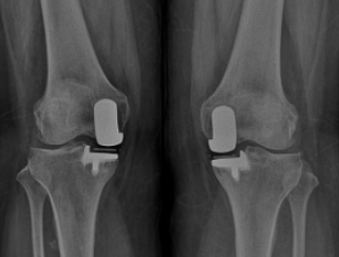

인공관절 수술은 단순히 손상된 관절을 교체하는 절차가 아니라, 새로운 관절로 ‘다시 걷는 삶’을 준비하는 시작점입니다. 그러나 많은 환자들이 수술 후 관리의 중요성을 간과하곤 합니다. 실제로 수술 자체보다 회복 과정이 더 길고, 그에 따른 생활습관 관리가 수술의 성공 여부를 결정합니다. 수술 직후의 운동요법, 영양 섭취, 체계적인 회복프로그램은 인공관절의 수명과 움직임의 질을 좌우하는 핵심 요소입니다. 이번 글에서는 수술 후 어떤 운동을 어떻게 해야 하는지, 어떤 식단이 회복을 빠르게 돕는지, 그리고 병원에서 권장하는 단계별 회복 프로그램은 어떤 내용을 담고 있는지 전문적이고 현실적인 관점에서 자세히 알아보겠습니다.

회복프로그램은 운동요법과 영양관리를 통합한 ‘전인적 재활 시스템’입니다. 수술 직후부터 병원에서는 개인의 상태에 맞춘 프로그램을 구성합니다. 이 프로그램은 대체로 3단계로 나뉩니다.